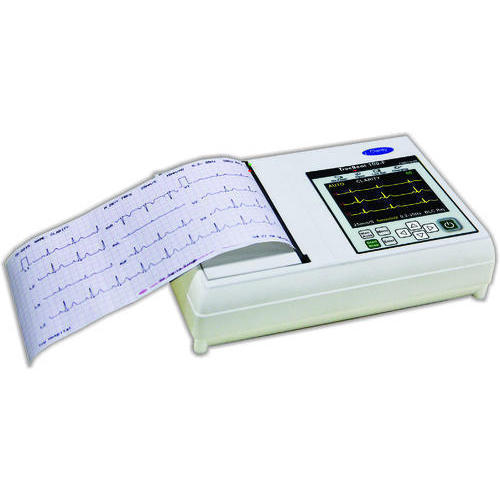

Blood cell counter, Electrical